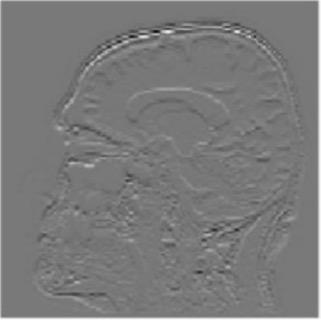

Image Pre-processing

Gray matter atrophy has been found to be responsible for MCI and AD progression (Apostolova et al., 2007). Pre-processing also standardizes the images. (Friston et al., 1994). Thus, pre-processing via segmentation and smoothing to capture just the gray matter of the MRI scans is necessary. The MRI scans were segmented using the Computational Anatomy Toolbox 12 (CAT 12) (Rajapakse et al., 1997) toolbox of MATLAB. These programs segmented the MRI images into grey matter, white matter, and cerebrospinal fluid. Figure 2 shows an unmodified MRI and a segmented MRI, which demonstrates the differences between them. After segmentation, the grey matter from each MRI scan was smoothed using the Statistical Parametric Mapping 12 (SPM12) (Friston et al, 1994) toolbox of MATLAB. These smoothed grey matter images were then sent for feature extraction.